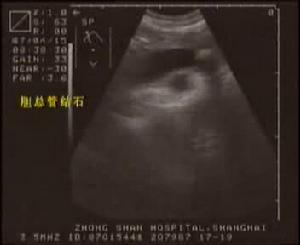

3.B型超声波检查虽然价廉无创,对胆囊结石的准确率达98%,但因受十二指肠等空腔脏器的影响,对胆总管结石的准确率仅为50%左右,特别对十二指肠后段胆管难以显示。假阳性及假阴性率均较高。 医学百科网 | YxBaike.Com